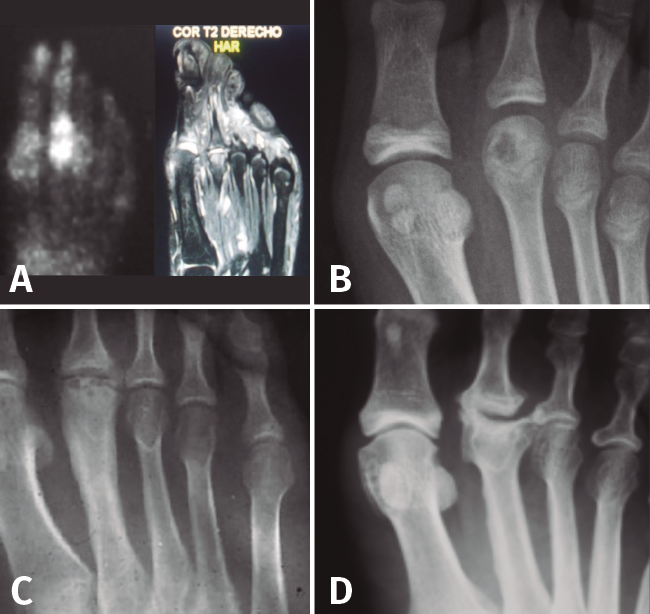

Figura 3. Fases evolutivas de la necrosis. A: fase inicial; B: fase de reparación; C: fase de repercusión articular; D: fase artrósica.

Como en todas las necrosis óseas, la radiología es característica y se corresponde con la fase evolutiva de la necrosis (Figura 3):

- Fase inicial en la que se produce la isquemia con la consiguiente muerte celular. En esta primera fase la radiología es negativa y el diagnóstico se establece con la ayuda de la gammagrafía y la resonancia magnética nuclear (RMN).

- Fase de reparación en la que existe una revascularización alrededor de la zona necrótica: vemos en la cabeza una zona más densa, que corresponde al hueso necrosado, y una zona radiolúcida alrededor de ella, que corresponde a la hiperemia.

- Fase de repercusión articular: el cartílago articular se hunde al fallarle el soporte mecánico del hueso subcondral.

- Fase artrósica en la que se ha producido la desestructuración de la articulación con pérdida del espacio articular y reacción osteofítica, tanto en la cabeza del metatarsiano como en la base de la falange.

Figura 4. Estadios de Smillie. A: estadio I; B: estadio II; C: estadio III; D: estadio IV; E: estadio V.

Basándose en la historia natural de la enfermedad y atendiendo a los cambios radiológicos, Smillie(16) clasifica, con propósito terapéutico, la lesión en 5 estadios (Figura 4):

- Estadio 1: aparece una línea de fractura a través de la epífisis.

- Estadio 2: se produce una depresión central de la cabeza por colapso del hueso subcondral. El espacio articular puede ensancharse.

- Estadio 3: la depresión central hace que se proyecten hacia delante los bordes medial y lateral de la cabeza, manteniéndose intacta la parte plantar.

- Estadio 4: la parte central necrosada de la cabeza puede desprenderse de la parte plantar, formándose un cuerpo libre articular.

- Estadio 5: aplanamiento de la cabeza metatarsal y van apareciendo los cambios degenerativos secundarios.